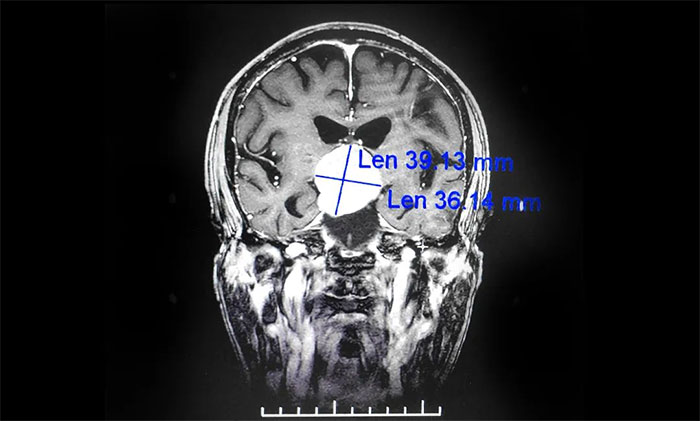

▲ 鞍区囊性占位病变

通过进一步完善头颅磁共振检查,提示患者鞍区囊性占位病变,考虑为颅咽管瘤,瘤体最大直径超过4cm。